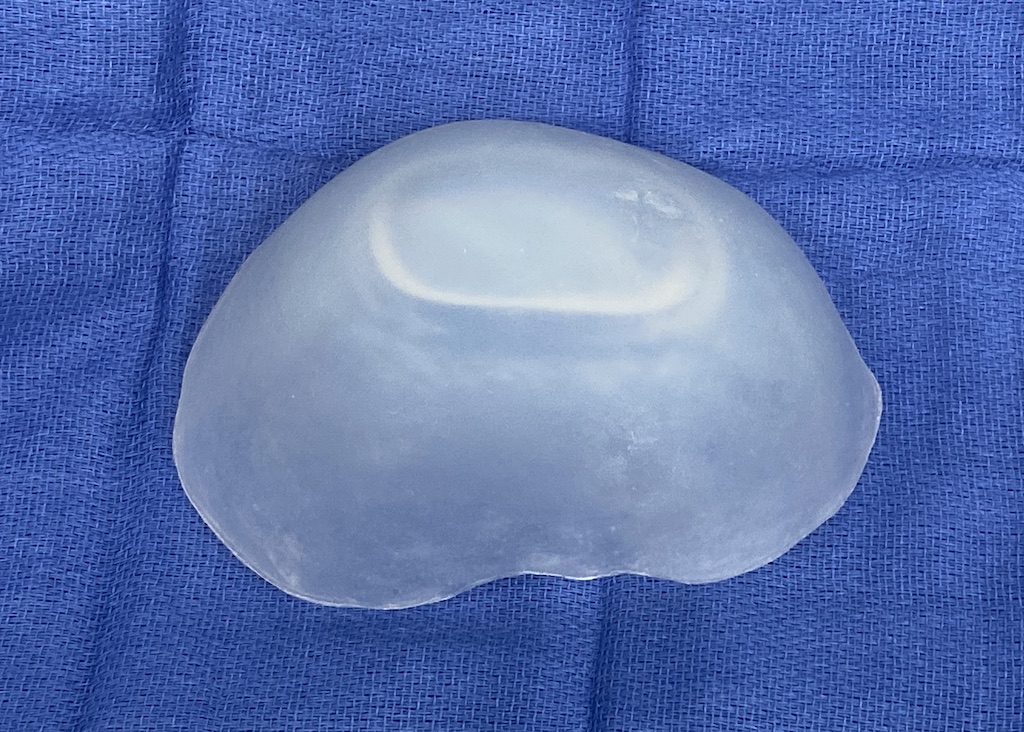

Desire to build up the flatter upper part of the back of his head.

Upper occipital skull augmentation using a custom skull implant.

Desire to build up the flatter upper part of the back of his head.

Upper occipital skull augmentation using a custom skull implant.